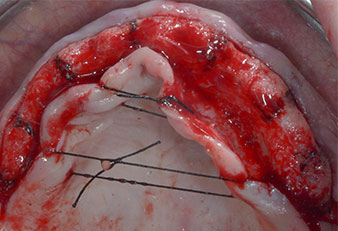

Debido al hueso relativamente duro (D2) existente en el sector anterior, los sitios de los implantes largos de 10 mm de las posiciones 11 y 21 se finalizaron con una fresa rotatoria de 4 mm de diámetro, en combinación con un contra-ángulo quirúrgico WS-75 L de W&H, el motor de implantes Implantmed de W&H y el módulo opcional Osstell ISQ de W&H. En cambio, debido a la existencia de hueso blando, los sitios posteriores se prepararon hasta un diámetro final de 3 mm utilizando el inserto Piezomed I3P. Por último, los implantes se colocaron a nivel crestal para su osteointegración durante tres meses (figuras 6-10). La prótesis existente se mantuvo sobre cuatro implantes provisionales (figura 8).